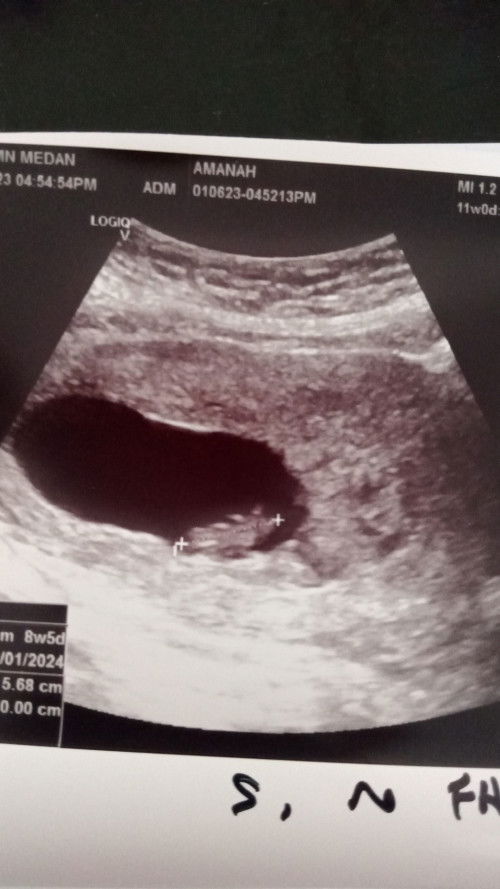

Baby kecik dan tak nampak heartbeat

Ada tak mommies yg pernah alami kes mcm sy? smlm pegi KK utk 1st check up, doc nk scan tgk jantung bby... tp bila scan patut dah 11w tapi scan detect baru 8w5d pastu jantung baby pun tak nmpak... sy tak tau nk rasa apa.. sbb sy mls nak layan rasa down tu. Boleh share experience mommies? Terima kasih. #bantusharing #pleasehelp #ingintahu #seriusnanya